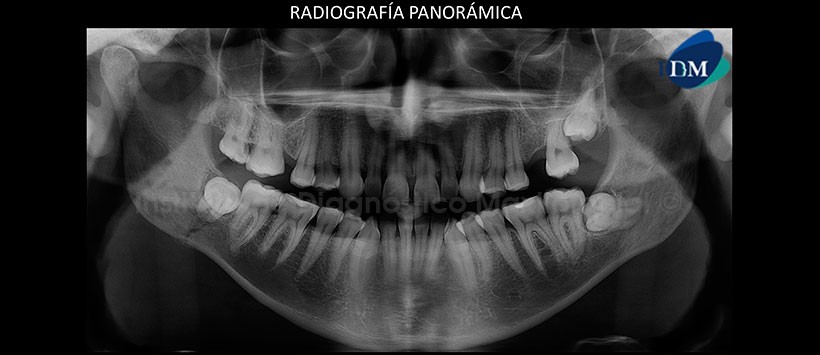

A la evaluación de la radiografía panorámica se aprecia un leve aplanamiento del contorno de cóndilo mandibular de lado izquierdo, ausencias de piezas dentarias y las piezas 28 y 38 impactadas en posición mesioanguladas. Siendo lo más resaltante la presencia de un trazo radiolúcido proyectado en zona antegonial de lado derecho, el cual se extiende desde la basal mandibular hasta la pieza 48 la cual esta impactada (En posición mesiaongulada). Así mismo se aprecia una leve reacción periostal próximo a la basal mandibular. (Figura 1)